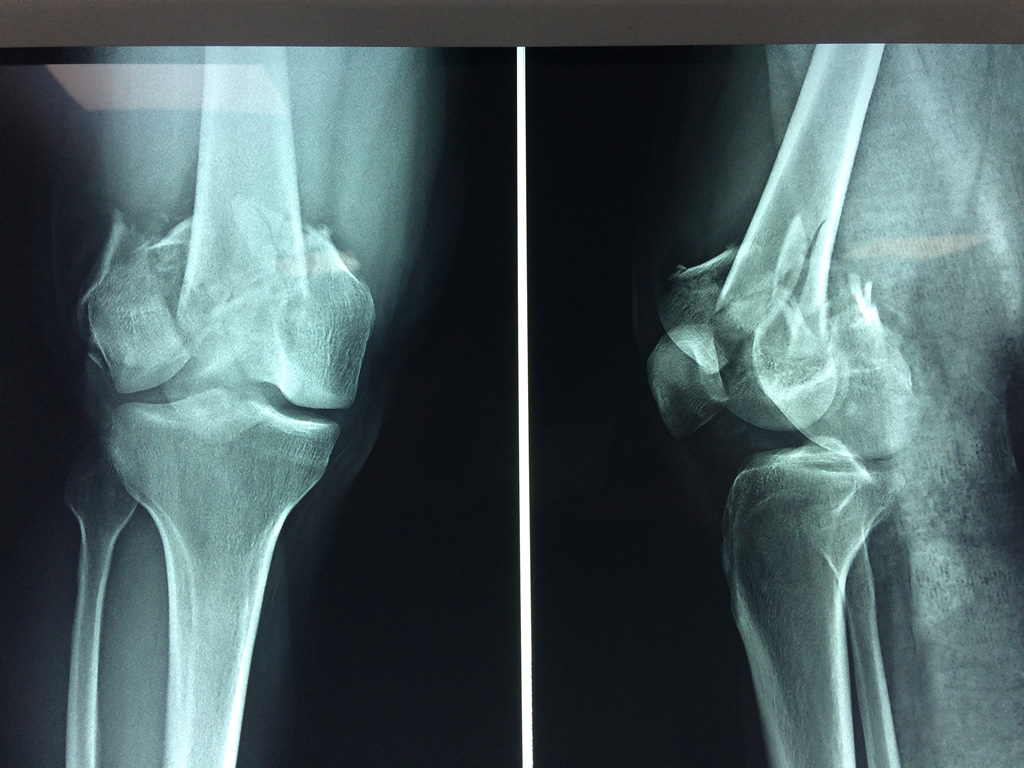

Fémur - Fémur

El fémur es el hueso del muslo, el segundo segmento del miembro inferior. Es el hueso más largo, fuerte y voluminoso del cuerpo humano.